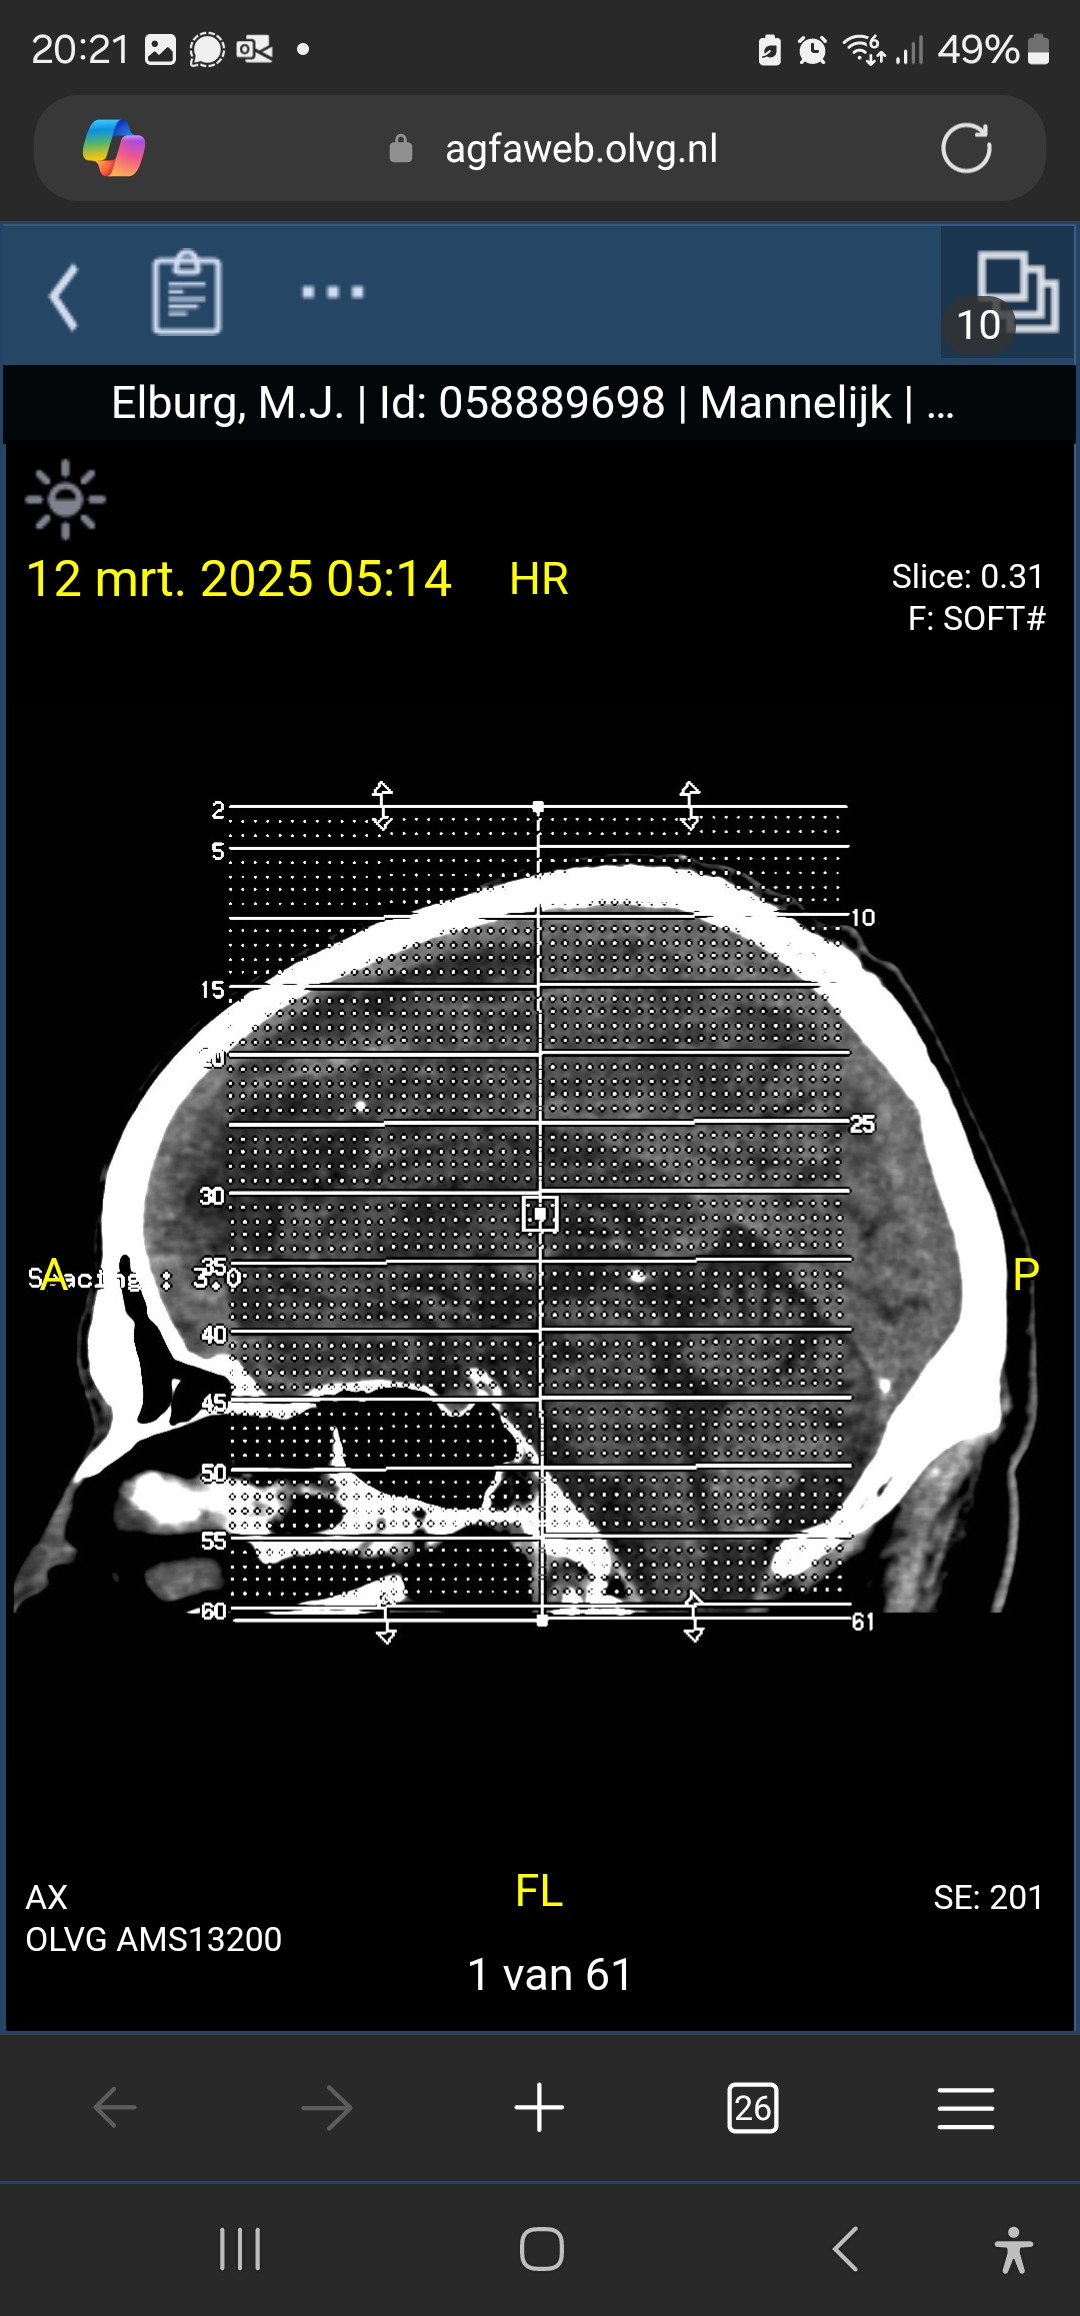

Heb naast de ct scan een mri van de hersenpan achter de rug maandag de uitslag.